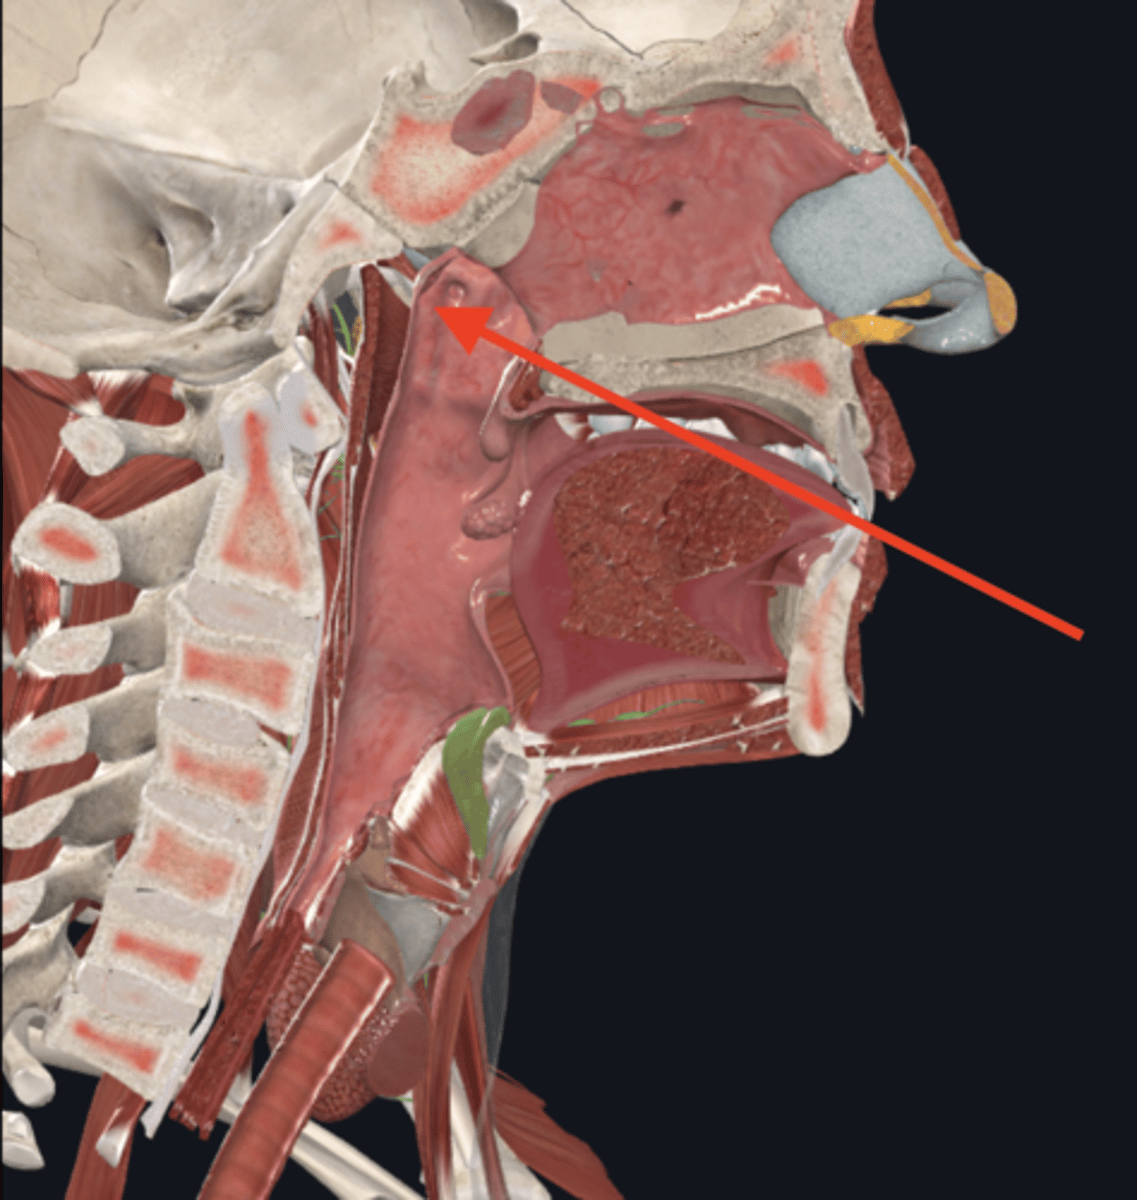

nasopharynx

name the circled region

oropharynx

name the circled region

laryngopharynx

name the circled region